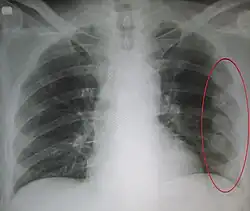

| An X ray showing multiple old fractured ribs of the person's left side as marked by the oval | |

Illustration showing rib fracture at 3rd, 4th and 5th rib -

Right sided pneumothorax and rib fractures -

Two broken ribs as seen on parasagittal CT